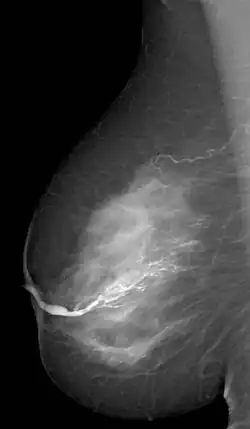

Die Galaktographie (altgriechisch γάλα gála „Milch“ [Genitiv γάλακτος gálaktos] und -graphie) ist ein mammografisches Zusatzverfahren zur Darstellung der Milchgänge. Zu diesem Zweck wird ein wasserlösliches, nichtionisiertes Kontrastmittel mit Hilfe einer Spritze mit Kanüle in den sekretierenden Milchgang gespritzt, eventuell unter lokaler Betäubung. Anschließend werden Röntgenaufnahmen in drei Ebenen angefertigt. Das Untersuchungsergebnis wird als Galaktogramm bezeichnet und stellt Veränderungen innerhalb der Milchgänge dar.

Indikation für eine Galaktographie ist ein blutiges Sekret aus der Brustwarze. Die Galaktografie dient dazu, einen Tumor oder ein Papillom im Milchgang zu entdecken und zu lokalisieren, damit die Veränderung in einer anschließenden Operation entfernt werden kann.